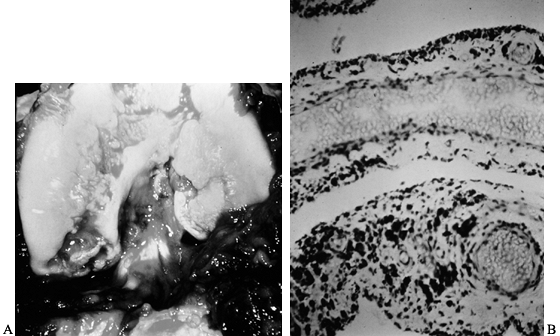

Gross and microscopic examination of hemophilic arthropathy reveals

destruction of articular cartilage by direct synovial invasion and

subchondral synovial and degenerative cysts. Biochemical studies have

documented enzymatic degradation similar to other forms of inflammatory

arthritis (6,66). Symmetry is common, and in that sense, the condition is similar to rheumatoid arthritis.

Figure 136.2. A: Photograph of the knee of the patient in Figure 136.1

at the time of open synovectomy a few days after the x-ray studies were taken. There is extensive hyperplastic synovitis with full-thickness erosion of the articular surface of the weight-bearing surfaces of the medial and lateral condyles and the trochlea. This demonstrates the advanced destruction that can occur with chronic hemophilic synovitis despite a relatively benign-appearing x-ray study. B: Photomicrograph of the synovium from this patient showing hemosiderin pigment deposition on the surface taken up by the phagocytic synovial A cells. These cells migrate into the perivascular tissue of the subsynovial layer to return blood products to the general circulation. This patient was in the stage of chronic hemarthrosis, which is easy to understand with dilated venous channels immediately beneath the surface that are easily torn when the fragile, hypertrophic synovium gets caught between the eroded joint surfaces. (See also COLOR FIG. 136.2.) |

bleeding regardless of clotting factor level (Fig. 136.1, Fig. 136.2). Muscles atrophy, joint contractures develop, and the patient becomes severely disabled (Fig. 136.3, Fig. 136.4).

unsuspected based on the plain radiographs (Fig. 136.1 and Fig. 136.2). With the